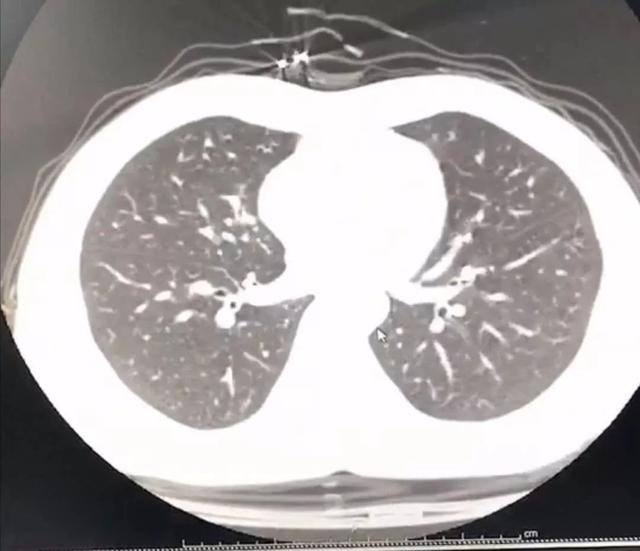

建议我还是去查一个肺部 CT 更放心一些。

于是拖着沉重的步伐,我又从家里出发去医院做胸部 CT 。幸运的是肺部还没有出现病毒性肺炎的特征性影像学表现,说明就算是新型冠状病毒感染,目前还属于轻型,没有实质性地累及肺组织。

图片来源:作者提供